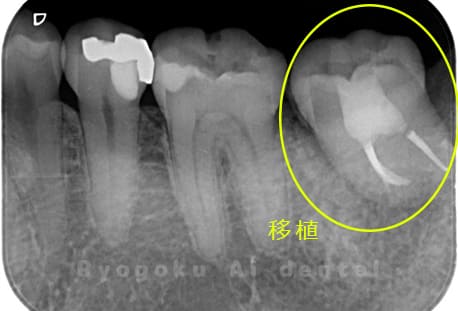

Case14

- 原因

- 重度カリエス、親知らず

- 治療内容

- 親知らずの抜歯、移植手術、マイクロエンド、ダイレクトボンディング

- 治療費用

- 220,000円

他院で親知らずと共に抜歯と診断された患者様です。親知らずの抜歯の必要性と左下奥歯の保存を試みた場合、歯の状態から根管治療、歯周外科、補綴の必要性から、移植治療を選択されました。大きな問題もなく、治療後も経過良好です。

<リスク・副作用>

治療後、痛みや違和感、出血、腫れなどが出る事があります。喫煙者、糖尿病などの方の場合、歯が生着しない場合があります。